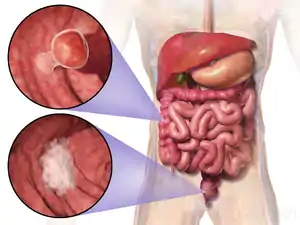

| Location and appearance of two example colorectal tumors | |

Colorectal cancer (CRC), also known as bowel cancer, colon cancer, or rectal cancer, is the growth of abnormal cells in the colon or rectum of the large bowel.[7] It has the ability to invade or spread to other parts of the body.[8] Symptoms may include blood in the stool, change in bowel movements, weight loss, feeling tired, and abdominal pain.[9]

Most colorectal cancers are due to old age and lifestyle factors, with only a small number of cases due to underlying genetic disorders.[3] Other risk factors include diet, obesity, smoking, and lack of physical activity.[9] Dietary factors that increase the risk include red meat, processed meat, and alcohol.[9] Other risk factors include radiation treatment to the pelvis, and inflammatory bowel diseases Crohn's disease and ulcerative colitis.[9] Some of the inherited genetic disorders that can cause colorectal cancer include familial adenomatous polyposis and hereditary non-polyposis colon cancer; however, these represent less than 5% of cases.[3] It typically starts as a benign tumor, often in the form of a polyp, which over time becomes cancerous.[9] Colorectal cancers can be generally divided by where in the bowel it occurs; right-sided, left sided and rectal.[9]

The polyp to cancer progression sequence is the classical model of colorectal cancer pathogenesis.[57] The polyp to cancer sequence describes the phases of transition from benign tumours into colorectal cancer over many years.[57] Central to the polyp to CRC sequence are gene mutations, epigenetic alterations and local inflammatory changes.[57] The polyp to CRC sequence can be used as an underlying framework to illustrate how specific molecular changes lead to various cancer subtypes.[57]